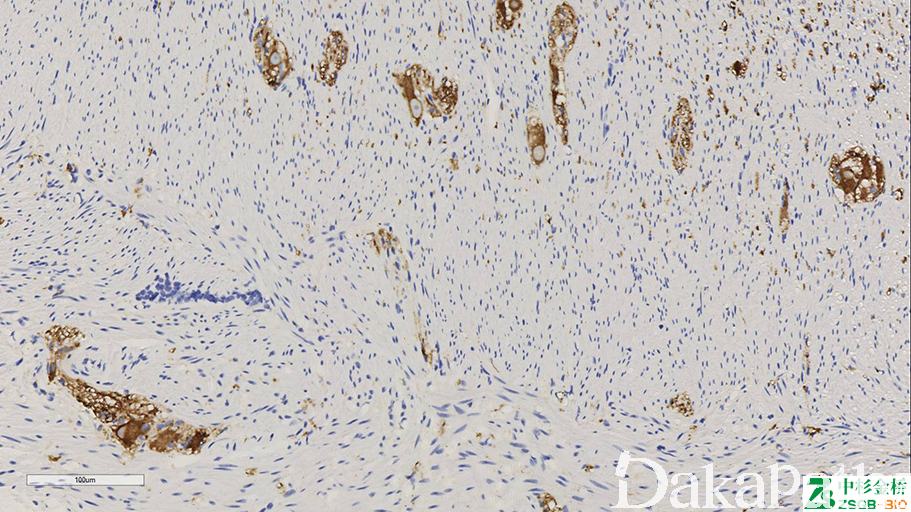

NSE

标记神经元、神经内分泌细胞及其肿瘤。

信号定位: 胞质